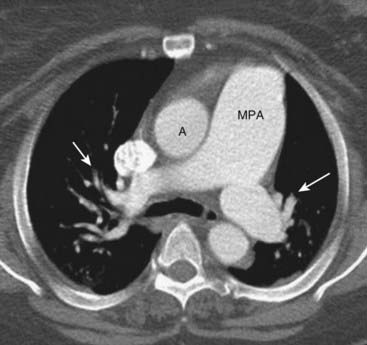

image The hallmark of pulmonary arterial hypertension is a discrepancy in size between the central pulmonary vasculature (i.e., the main, right, and left pulmonary arteries are large) and the peripheral pulmonary vasculature. This discrepancy is called pruning.

image On CT scans, the main pulmonary artery is normally about the same diameter as the ascending aorta, but in pulmonary arterial hypertension the main pulmonary artery is usually 3 cm or larger in size (Fig. 9-22).

Figure 9-22 Pulmonary arterial hypertension.

Normally, the main pulmonary artery (MPA) is about the same diameter as the ascending aorta (A). In this patient, with pulmonary arterial hypertension, the MPA is much larger than the aorta. There is also a rapid attenuation in the size of the pulmonary arteries (solid white arrows) called pruning, which is also seen in pulmonary arterial hypertension.